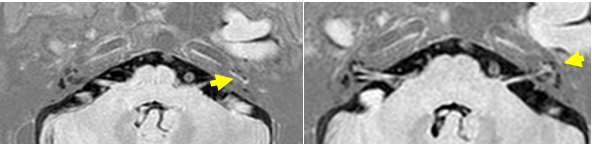

图为内耳钆造影MR,左侧耳蜗顶转、中转及前庭半规管未见明确显影

近半年来,赵先生眩晕发作频繁,经推荐,他从河北老家来到北京清华长庚医院耳鼻咽喉头颈外科副主任伊海金的门诊。在完善听力学相关检查及钆造影MR等辅助检查后,结果提示患者右耳极重度感音神经性耳聋、左耳重度感音神经性耳聋,左侧水平半规管功能降低,眩晕障碍量表显示躯体、情绪及功能严重障碍。结合问诊,伊海金诊断患者是由于迟发性膜迷路积水(DEH)导致的双侧严重的听力损失和前庭功能障碍。